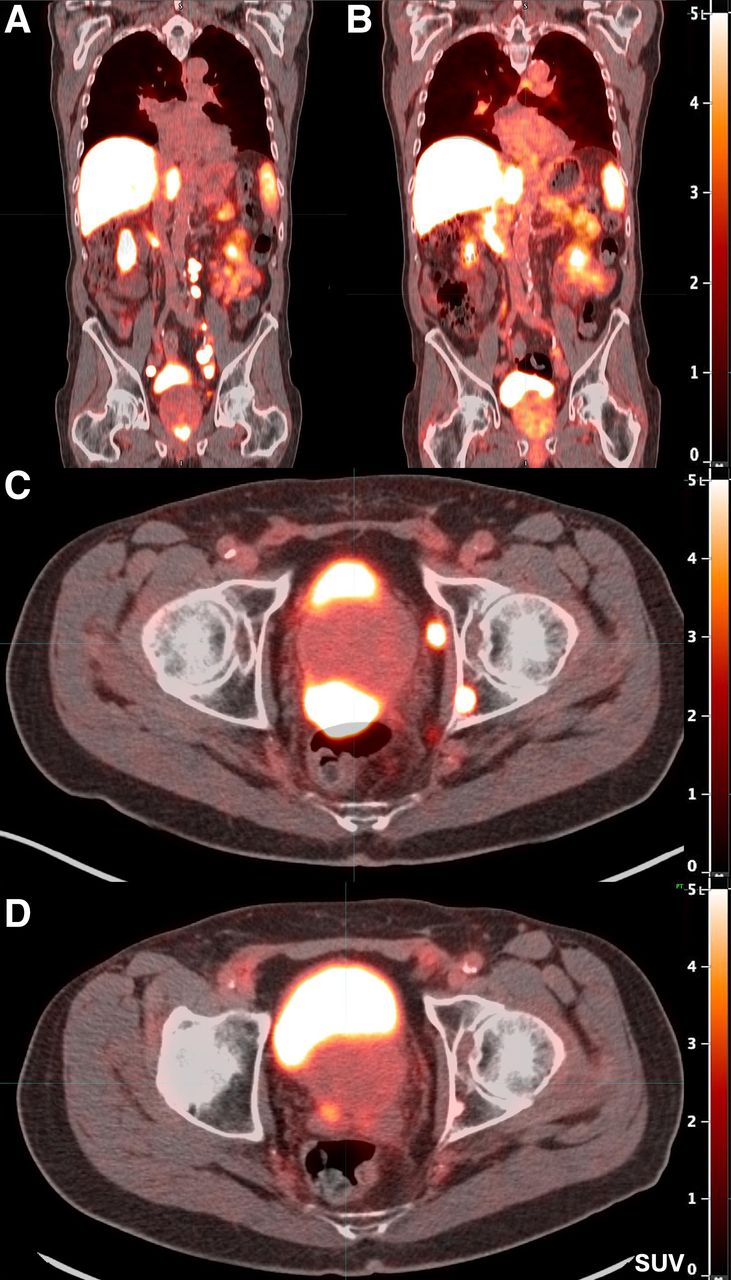

Pluvicto has met its primary endpoint in a phase III trial testing the treatment in men with prostate-specific membrane antigen (PSMA)-positive metastatic hormone-sensitive prostate cancer (mHSPC).

The findings are from an interim analysis of the open-label, prospective PSMAddition trial in which participants are receiving either Pluvicto in combination with standard of care (androgen receptor pathway inhibitor therapy and androgen deprivation therapy) or standard of care alone.

Pluvicto (lutetium-177 PSMA-617) was first approved in 2022 for adult patients with PSMA-positive metastatic castration-resistant prostate cancer who have previously received standard of care treatments. In May, it was approved for use after one androgen receptor pathway inhibitor (ARPI) treatment as well as prior to chemotherapy.